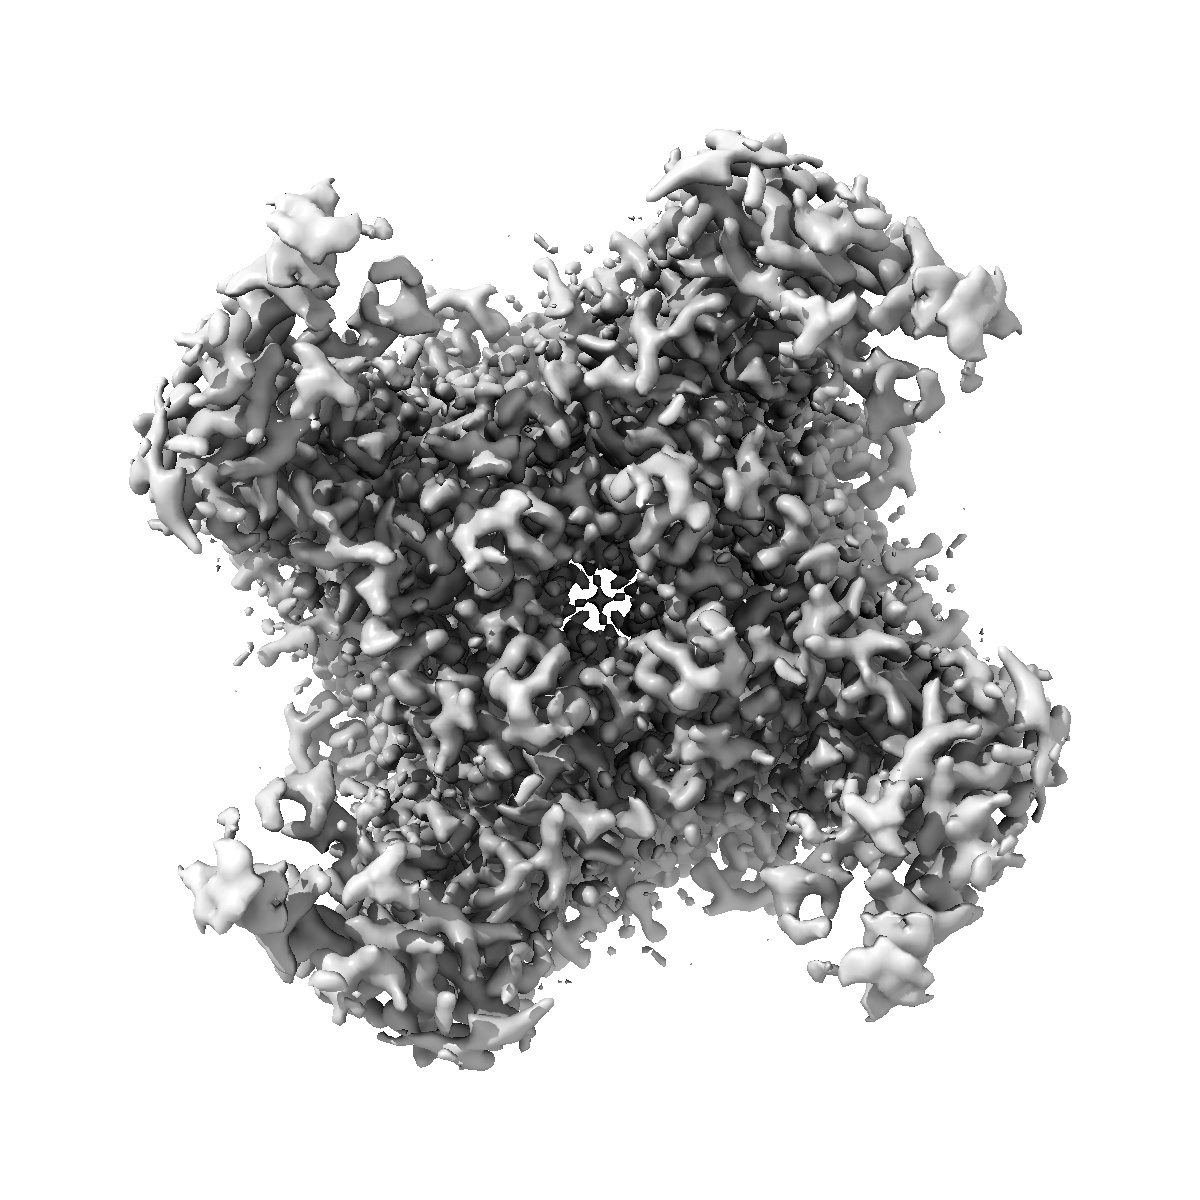

TRPML1 in complex with compound 5

EMD-52211

Single-particle2.1 Å

Sample: Mucolipin-1

High throughput cryo-EM provides structural understanding for modulators of the lysosomal ion channel TRPML1.